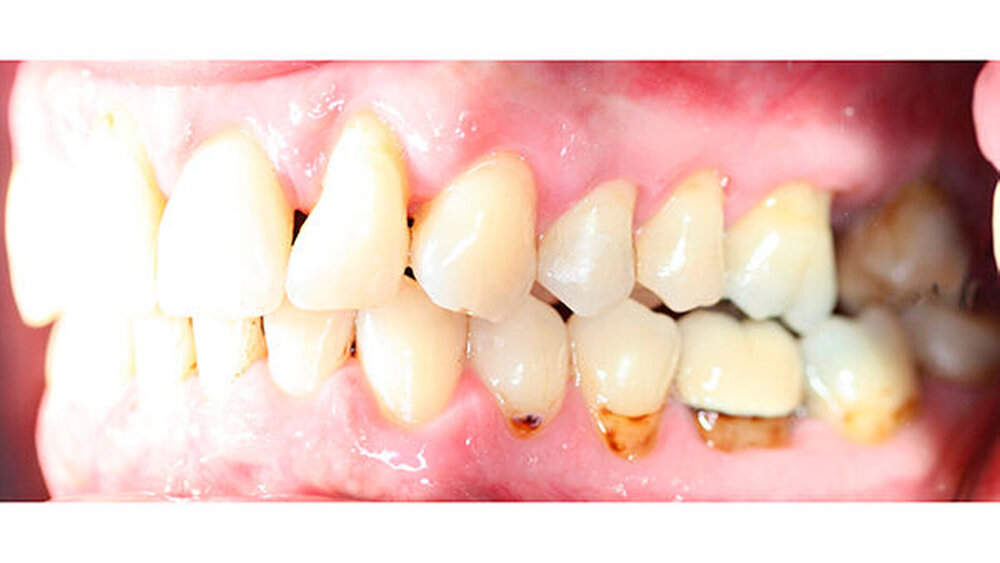

Um einen kompletten Lückenschluss im Oberkiefer zu ermöglichen, musste im Unterkieferfrontzahnbereich zusätzlich zur Derotation und Positionierung der Zähne - insbesondere Zahn 41 - von approximaler Schmelzreduktion, kurz ASR , Gebrauch gemacht werden, um einer Tonn`schen Diskrepanz entgegenzuwirken (Abbildung 4).